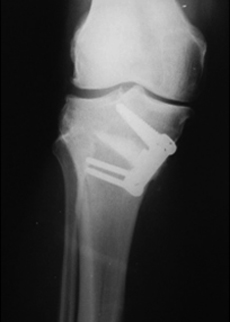

L'apertura osteotomica si blocca infine con un'apposita placca e 4 viti; se l'apertura e' di una certa entita' si puo' usare un trapianto di osso autologo od artificiale

Controllo a distanza di 1 anno che evidenzia l'ottima ricrescita ossea nella sede dell'osteotomia e l'ottimo allineamento dell'arto inferiore ottenuto con l'intervento